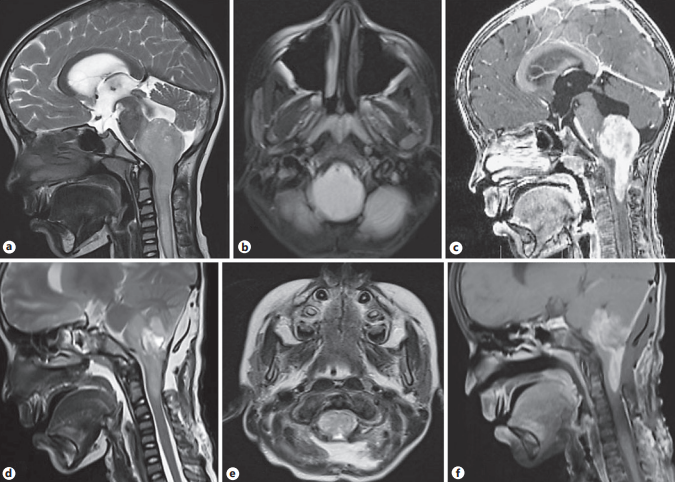

8岁男童,走路不稳持续3个月,声音嘶哑,流口水1个月。检查发现乳头水肿,小脑共济失调,腭运动障碍,呕吐反射消失。四肢力量正常,深腱反射明显。脑和脊柱MRI显示一个膨胀性病变,累及髓质,延伸至颈髓C2水平,t2加权图像高信号,增强良好。远端颈髓水肿(图2a- c)。

他接受了中线枕下开颅术、C1弓切除、C2 C3椎板切开术和病变次全切除。术中肿瘤较硬,向C2水平延伸,导致脊髓和脑干变宽,肿瘤与正常组织之间无明显平面。在体感和运动诱发电位(SSEP和MEP)监测下行脊髓和脑干肿瘤次全减压术。肿瘤的组织学是典型的报告,他年级即BRAF V600E突变由免疫组织化学染色是的(图3 a、b)。术后脑部MRI显示髓质残余病灶,减少在质量效应(图2 d -f),术后6个月,他已经持续降低颅神经麻痹,并与完整ambulant肢体的力量。气管造口术和经皮胃造口术用于呼吸护理和营养。